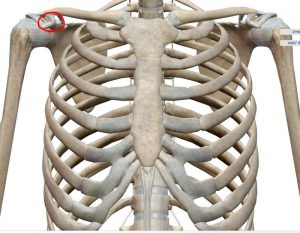

実はこの小胸筋という筋肉は体の前側にあるのですが、肩甲骨の上の方「烏口突起(うこうとっき)」という場所についていて、筋肉が縮こまると肩甲骨を前側に傾かせてしまいます。

肩甲骨が前に傾くと、肩が本来のポジションでなくなってしまうので、きちんとバンザイの動作ができなくなってしまいます。